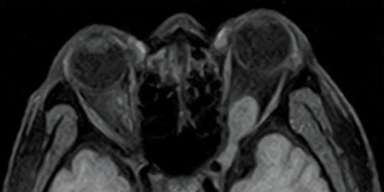

FSE-RADAR DWI

STIR

RADAR uses radial scan technology to mitigate motion artefact caused by a patient’s body movement due to voluntary or involuntary motion. Available with T2WI but also T1WI and FLAIR imaging in various plane and various body region including the head and shoulder joint, which are susceptible to respiration movements and the cervical spine that can be affected by swallowing movements. RADAR can help reduce repeat scans and improve image quality.